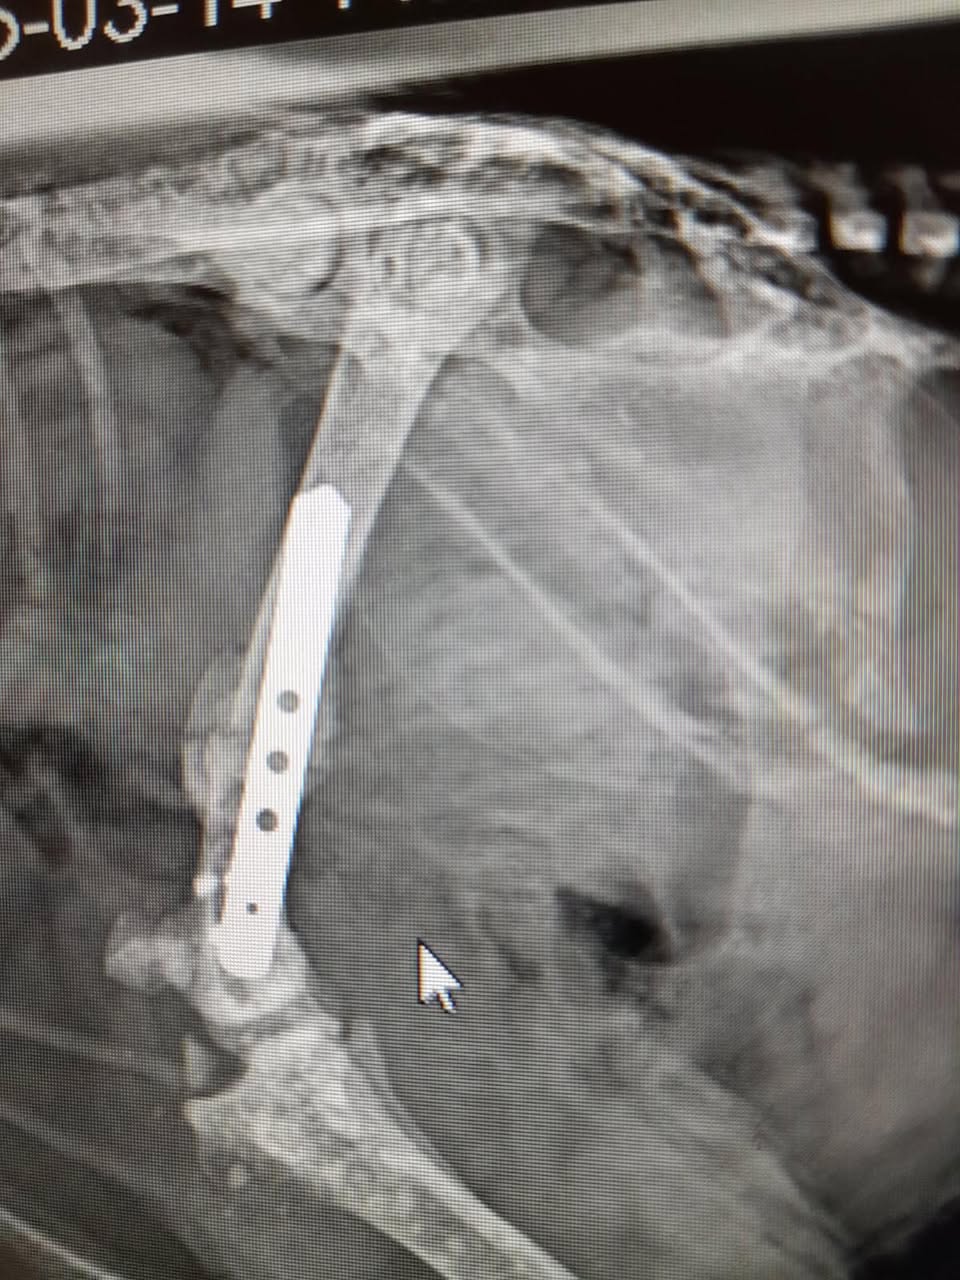

Dynamo Betty broke her leg here in a freak accident when she was in a fight with another chicken last month. Surgery went great and she came home ready to heal. Sadly an x-ray a week later showed the plate had moved, also moving the bone position. So, I walked around with Dynamo with her leg in this position for weeks, even having her in a sling around my waist trying to give the bone more of a chance to heal. She is an uber active hen and all this has been so frustrating for her and she’s fed up. Last week she got vet clearance to be able to do more things and Friday sees her go in for another x-ray and fingers crossed we have a healing bone.

She had surgery on her broken leg on Feb 11. Due to the plate moving slightly, her healing has taken longer than normal but Friday’s x-ray showed that it’s finally formed a callous! Hallelujah! It’s been a long and frustrating journey for us both.